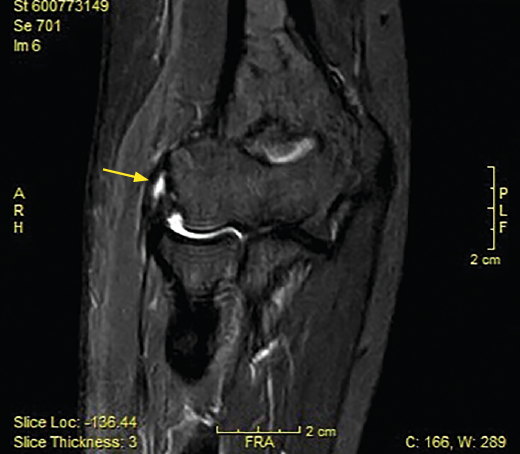

Figura 6. En este examen longitudinal del tendón extensor común (T. extensor), se describen los signos ecográficos de una epicondilopatía: el aumento de grosor del tendón y la pérdida de su patrón fibrilar con áreas de pequeña rotura en su interior (flechas). Imagen cedida por el Dr. Fernando Jiménez Díaz.

La resonancia magnética (RM) permite identificar cambios que incluyen el aumento de la señal del tendón dentro o alrededor de la inserción, engrosamiento del tendón o una discreta colección de líquido entre la cápsula lateral y el tendón extensor (Figura 8). La mayoría de los pacientes con síntomas de tendinopatía lateral crónica muestran cambios de señal en la RM y se ha podido relacionar la proporcionalidad entre la severidad de los cambios y la sintomatología del paciente(17). Ofrece ciertas ventajas frente al resto, como el hecho de que es más reproducible, reduce la variabilidad interobservador y ofrece más información acerca de la patología intraarticular(18). En ciertos entornos, sin problemas para obtener RM de calidad en periodos cortos de tiempo, se utiliza la RM para cuantificar el espesor de la lesión y la localización superficial o profunda de la misma y en función de dichos hallazgos planificar un abordaje abierto o artroscópico. En medios con dificultades para obtener RM en todas las sospechas de tendinopatía lateral de codo(19), la ecografía puede ser útil para diagnosticar de manera adecuada esta patología en la mayoría de los pacientes, lo que permite reservar la RM para pacientes con síntomas cuyos hallazgos ecográficos sean normales.(20).

Figura 8. Cambios vistos en resonancia magnética en paciente con dolor en la cara lateral del codo. Aumento de la señal del tendón dentro (flecha) o alrededor de la inserción, engrosamiento del tendón y una discreta colección de líquido entre el ligamento colateral lateral.